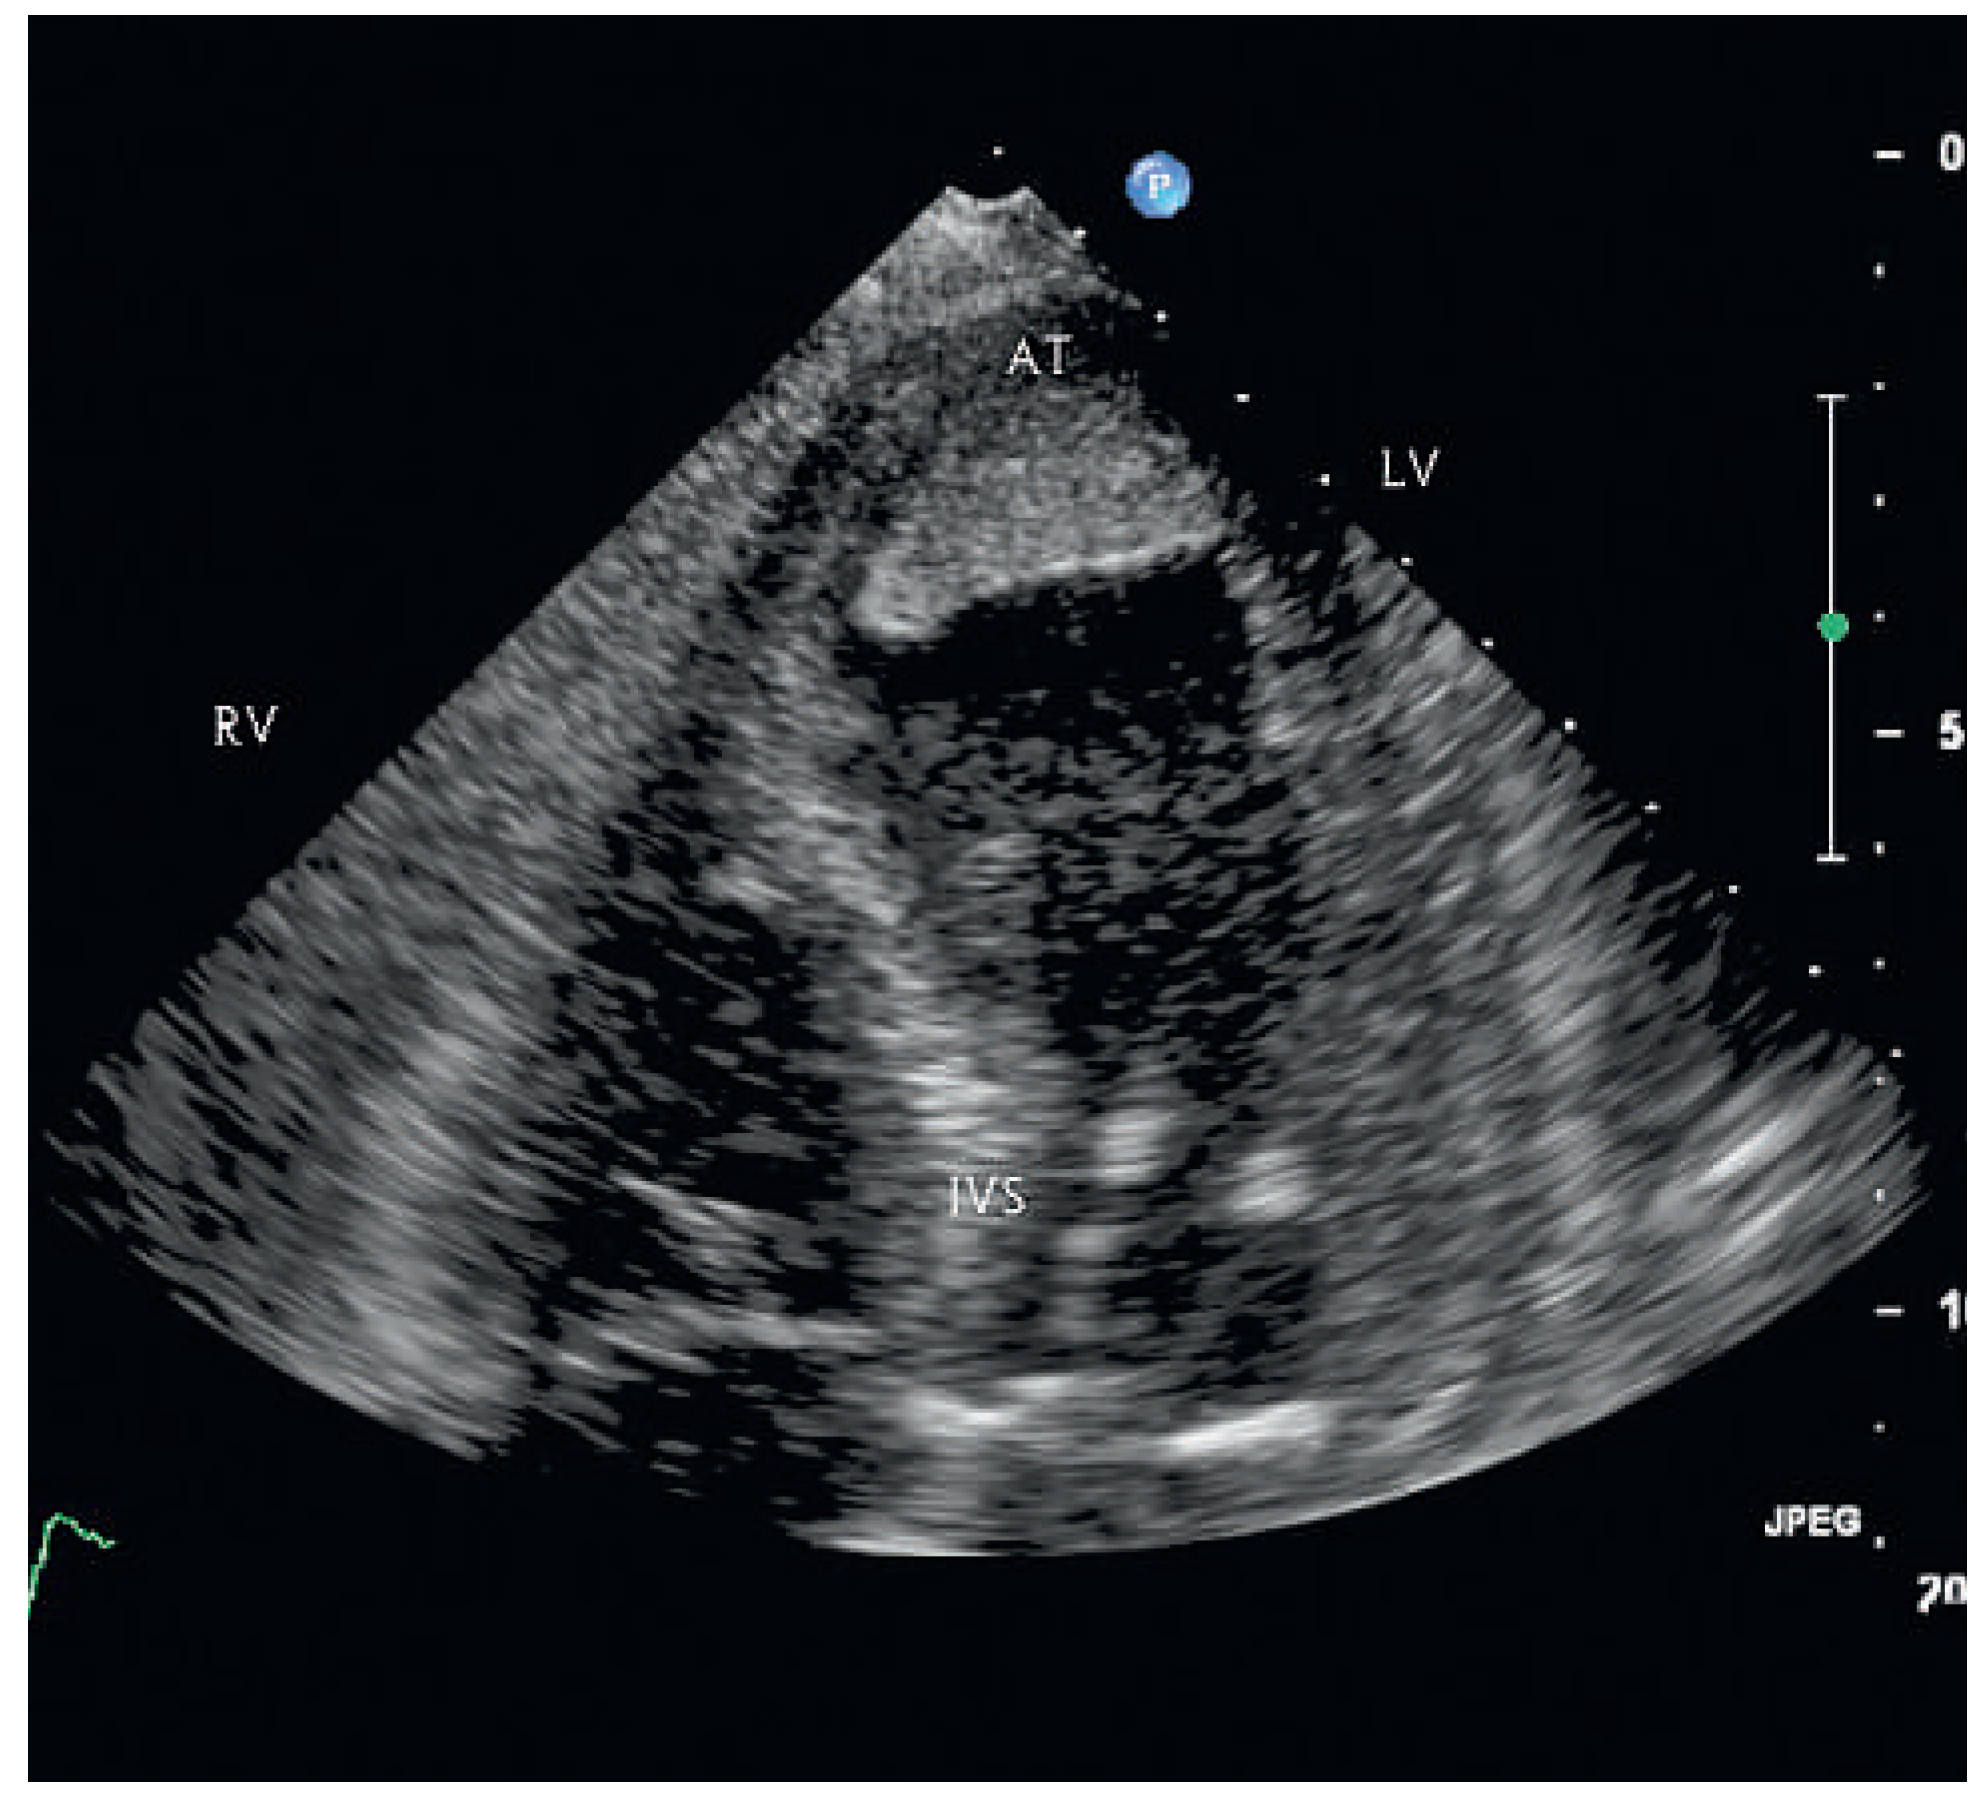

A 87-year-old female patient was hospitalised for decline in general health status, fatigue and oedema following a fall two weeks earlier. On no occasion did the patient experience chest pain or shortness of breath. The blood pressure and heart rate on admission were 113/79 mm and 80 bpm Hg respectively. Cardiopulmonary auscultation revealed a harsh, loud holosystolic murmur most audible along the left sternal border and radiating to the base, apex and right parasternal area, with accentuation of the second heart sound and crepitus rales across all lung fields. Bilateral ankle oedema was present without distention of the jugular veins. The ECG was compatible with subacute anterior and inferior myocardial infarction. Echocardiography showed severely depressed left ventricular function in the presence of apical and anteroseptal dyskinesia and septal rupture with bidirectional shunt on colour Doppler. In addition, an apical thrombus and severe aortic stenosis with severe pulmonary hypertension were noted. In light of the patient’s age and the echocardiographic findings it was decided not to institute active treatment, and during the echocardiographic examination the patient developed profound cardiogenic shock and died.

Figure 1. Apical four chamber view of echocardiography showing apical thrombus. AT = apex with apical thrombus; LV = left ventricle; IVS = interventricular septum; RV = right ventricule.